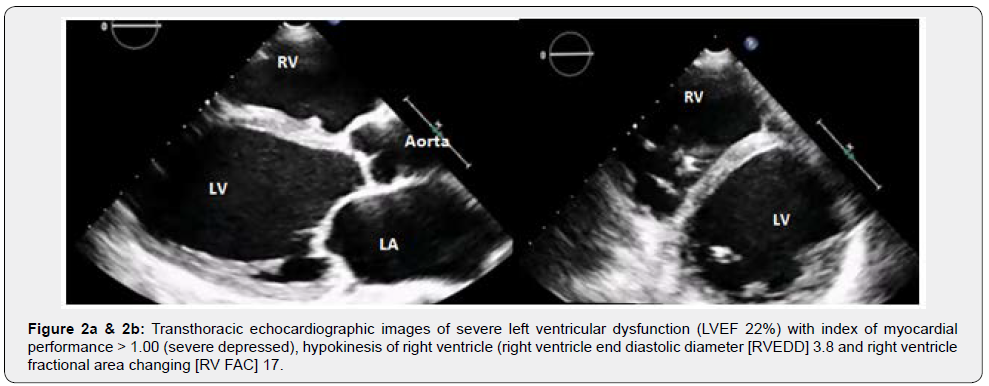

A 27year-old female (Body Surface Area [BSA] 1.67m2) developed progressive dyspnoea (NYHA functional class IIIb) 55 days after giving birth (spontaneous full-term delivery). She was admitted to Intensive Cardiology Unit and underwent to TransThoracic Echocardiogram (TTE) then Cardiac Magnetic Resonance Imaging (MRI) that documented severe left ventricular dysfunction (Left Ventricle Ejection Fraction [LVEF] < 25%, Figure 2a), hypokinesis of right ventricle (RV) (Figure 2b, Video 1). As a prophylaxis of sudden arrhythmic death, the patient received an implantable cardioverter defibrillator (ICD). The patient was treated with diuretics, vasodilators and oral anticoagulant therapy overlapping low molecular weight heparin (LMWH) until the achievement of therapeutic INR.After one month, she presented hepatic dysfunction secondary to heart failure, hence she was transferred to our Cardiovascular Intensive Care Unit with unstable hemodynamic (Arterial Pressure 80/50mmHg, Heart Rate 115 beats/minute), lactate acidosis (Lactate 4.5mmol/l) and slight dyspnoea. We started infusion of dobutamine (5mcg/kg/min), nitroprussiate (0.1mcg/kg/min) and furosemide (20mg/hour). Lab data evidenced severe deficit of antithrombin (AT III 26%) and coagulative C protein (36%), high levels of Factor VIII (>200%), DDimer test (3.618ng/ml), and Fibrinogen (390mg/dl) (Table 1). Thrombophilic screening showed eterozygotes phenotype for methylenetetrahydrofolate reductase (MTHFR) with normal homocysteinemia (6.3micron/l). The patient’s group blood was A, the test for Heparin Induced Thrombocytopenia (HIT) was initially negative.